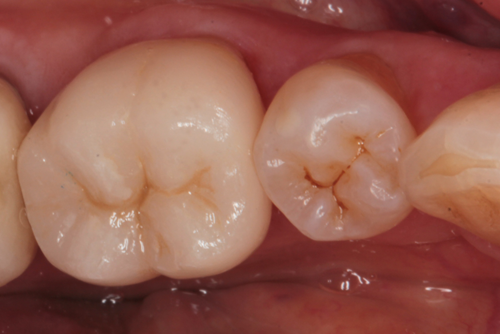

The crown and printed model were returned to my office. At the seating appointment, the provisional crown was removed and the final crown was tried in. Contacts, margins and occlusion were evaluated and no adjustments were needed. The crown was bonded to place using a self-adhesive resin cement (Fusion-ZR Dual Cure Resin Cement, Taub Products). It can be seen in place from the facial view in Figure 11 and the occlusal view in Figure 12. The radiograph in Figure 13 shows the excellent fit of the digitally fabricated crown.

Fig. 11 Fig. 12 Fig. 13